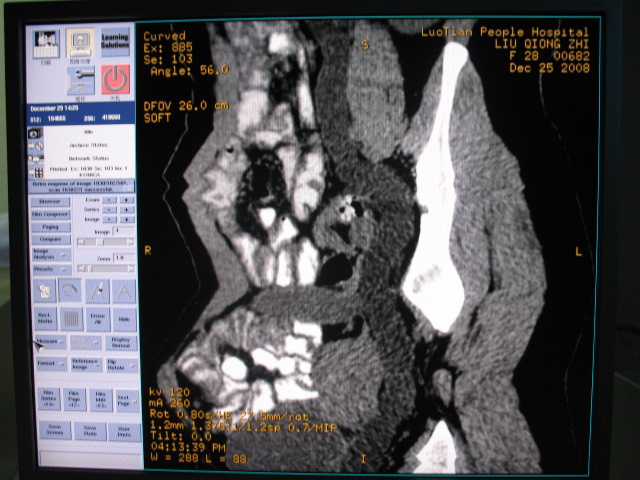

女,28岁,自觉腹部包块一年余

左侧为扩张的输尿管,一直延续到膀胱,那么它的上端应该是扩张的肾盂,但是在他的下方我们看到一个比较正常的肾,所以考虑左侧重复肾盂输尿管畸形。

考虑左侧双肾盂双输尿管畸形,其中一输尿管末端梗阻(不排除异位开口可能)并相应之肾盂及输尿管明显扩张积水。

术后证实是左侧双肾盂双输尿管畸形,巨输尿管巨肾盂症